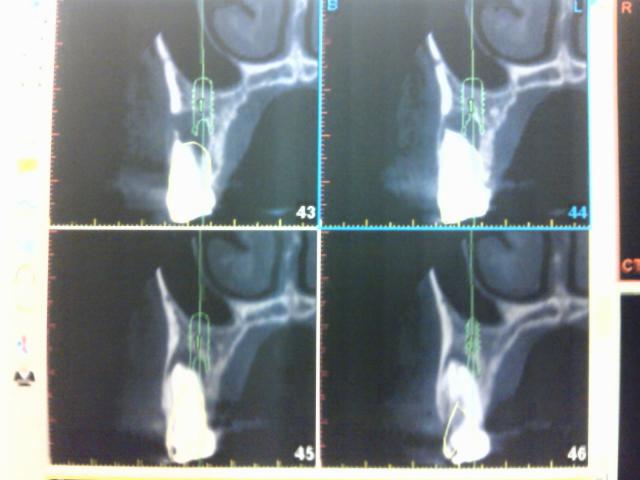

º¬ÀíÉÂÁ㤬¤¢¤ê

È´»õ¤ò¤·¤¿Éô°Ì¤Ë

¥¤¥ó¥×¥é¥ó¥È¤ò¿¢Î©¤·¤¿¡£

£Ã£Ô¤Ç¿ÇÃǤò£²¤«·îÁ°¤Ë¹Ô¤Ã¤¿¤È¤¤ÈÈæ³Ó¤¹¤ë¤È¹ü¤ÎºÆÀ¸¤¬Á᤯Æü³«¤¯´Êñ¤Ê¥ª¥Ú¤È¤Ê¤Ã¤Æ¤¤¤¿¡£

±¦¾å£´ÈÖ¡¡Ä¾·Â£´¡¥£¸Ð¡ß£±£°Ð¡¡£Ó£Ð¡¡

¥¹¥È¥í¡¼¥Þ¥ó¥¤¥ó¥×¥é¥ó¥È»ÈÍÑ